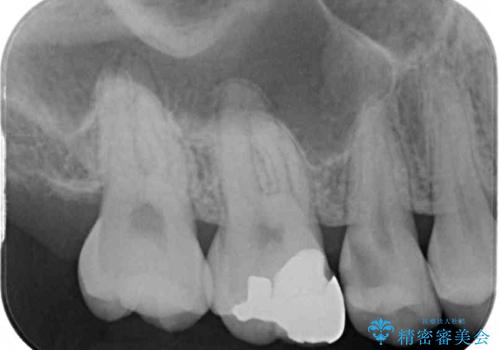

レントゲン写真より、第一小臼歯にやや大きい虫歯があることが分かりました。

症状などから診断したところ、神経を取る可能性は低いと考えられたため、セラミックインレーによる修復治療を行うこととしました。